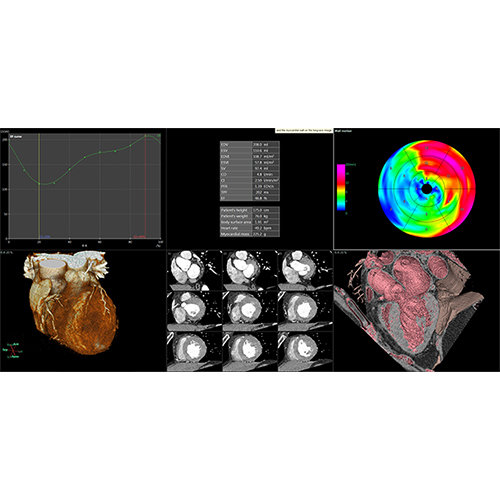

View X-Ray CT & MRI Scans Fast and Easily

Designed for surgeons, Pro Surgical 3D makes it easy to view patient scans quickly. Pro Surgical 3D facilitates the optimal 3D treatment and assessment workflows based on X-ray CT and MRI scans – and best of all, it’s FREE!

High-quality and fast 3D reconstruction and 3D rendering

Performs 3D reconstruction and volume rendering.

Multi-planar slicing.